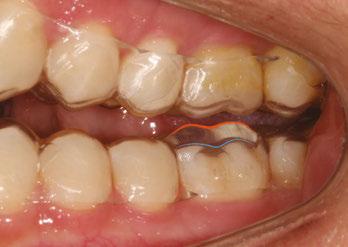

Figure 1: JA initial photos. Mixed dentition, Class I, upper spacing, lower crowding, ectopic U3s (10.7 years old)

Figure 3: Upper occlusal of the initial set-up versus upper occlusion clinical photo at 4 months

Figure 4: JA refinement records 4 months into treatment (10.11 years old). Upper and lower expanded. Refinement goals were to complete alignment and space consolidation and exaggerate U2 mesial root tip